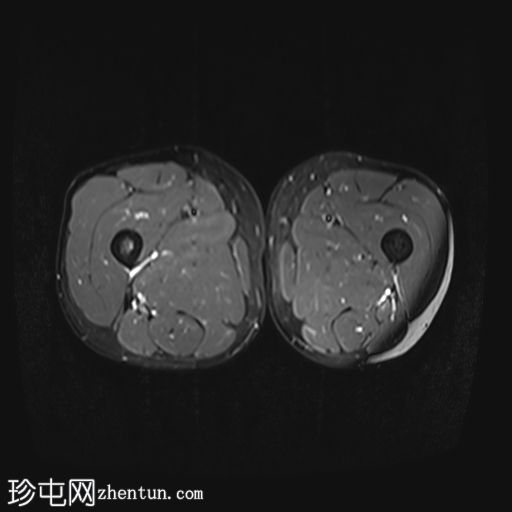

轴位

T1加权像

影像显示右侧阔筋膜张肌(TFL)拉伤,伴有水肿,阔筋膜浅层受累。

右侧缝匠肌也可见轻度拉伤,肌间液在股直肌、缝匠肌和阔筋膜张肌之间流动。

此外,筋膜水肿沿髂胫束向下延伸,髂胫束是一条从髂嵴延伸至胫骨外侧的厚筋膜带。

未见局灶性纤维断裂或肉眼可见的撕裂。未见血肿。